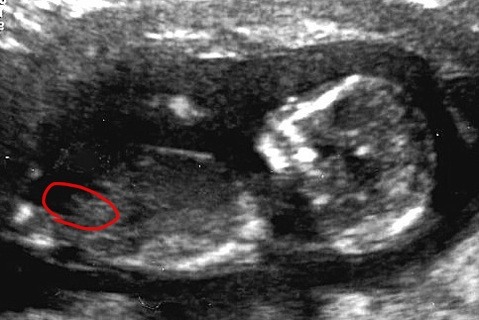

This is where we were looking. Is this the cord insertion? And she just had an ultrasound confirming boy this morning :)

Attachment 6606